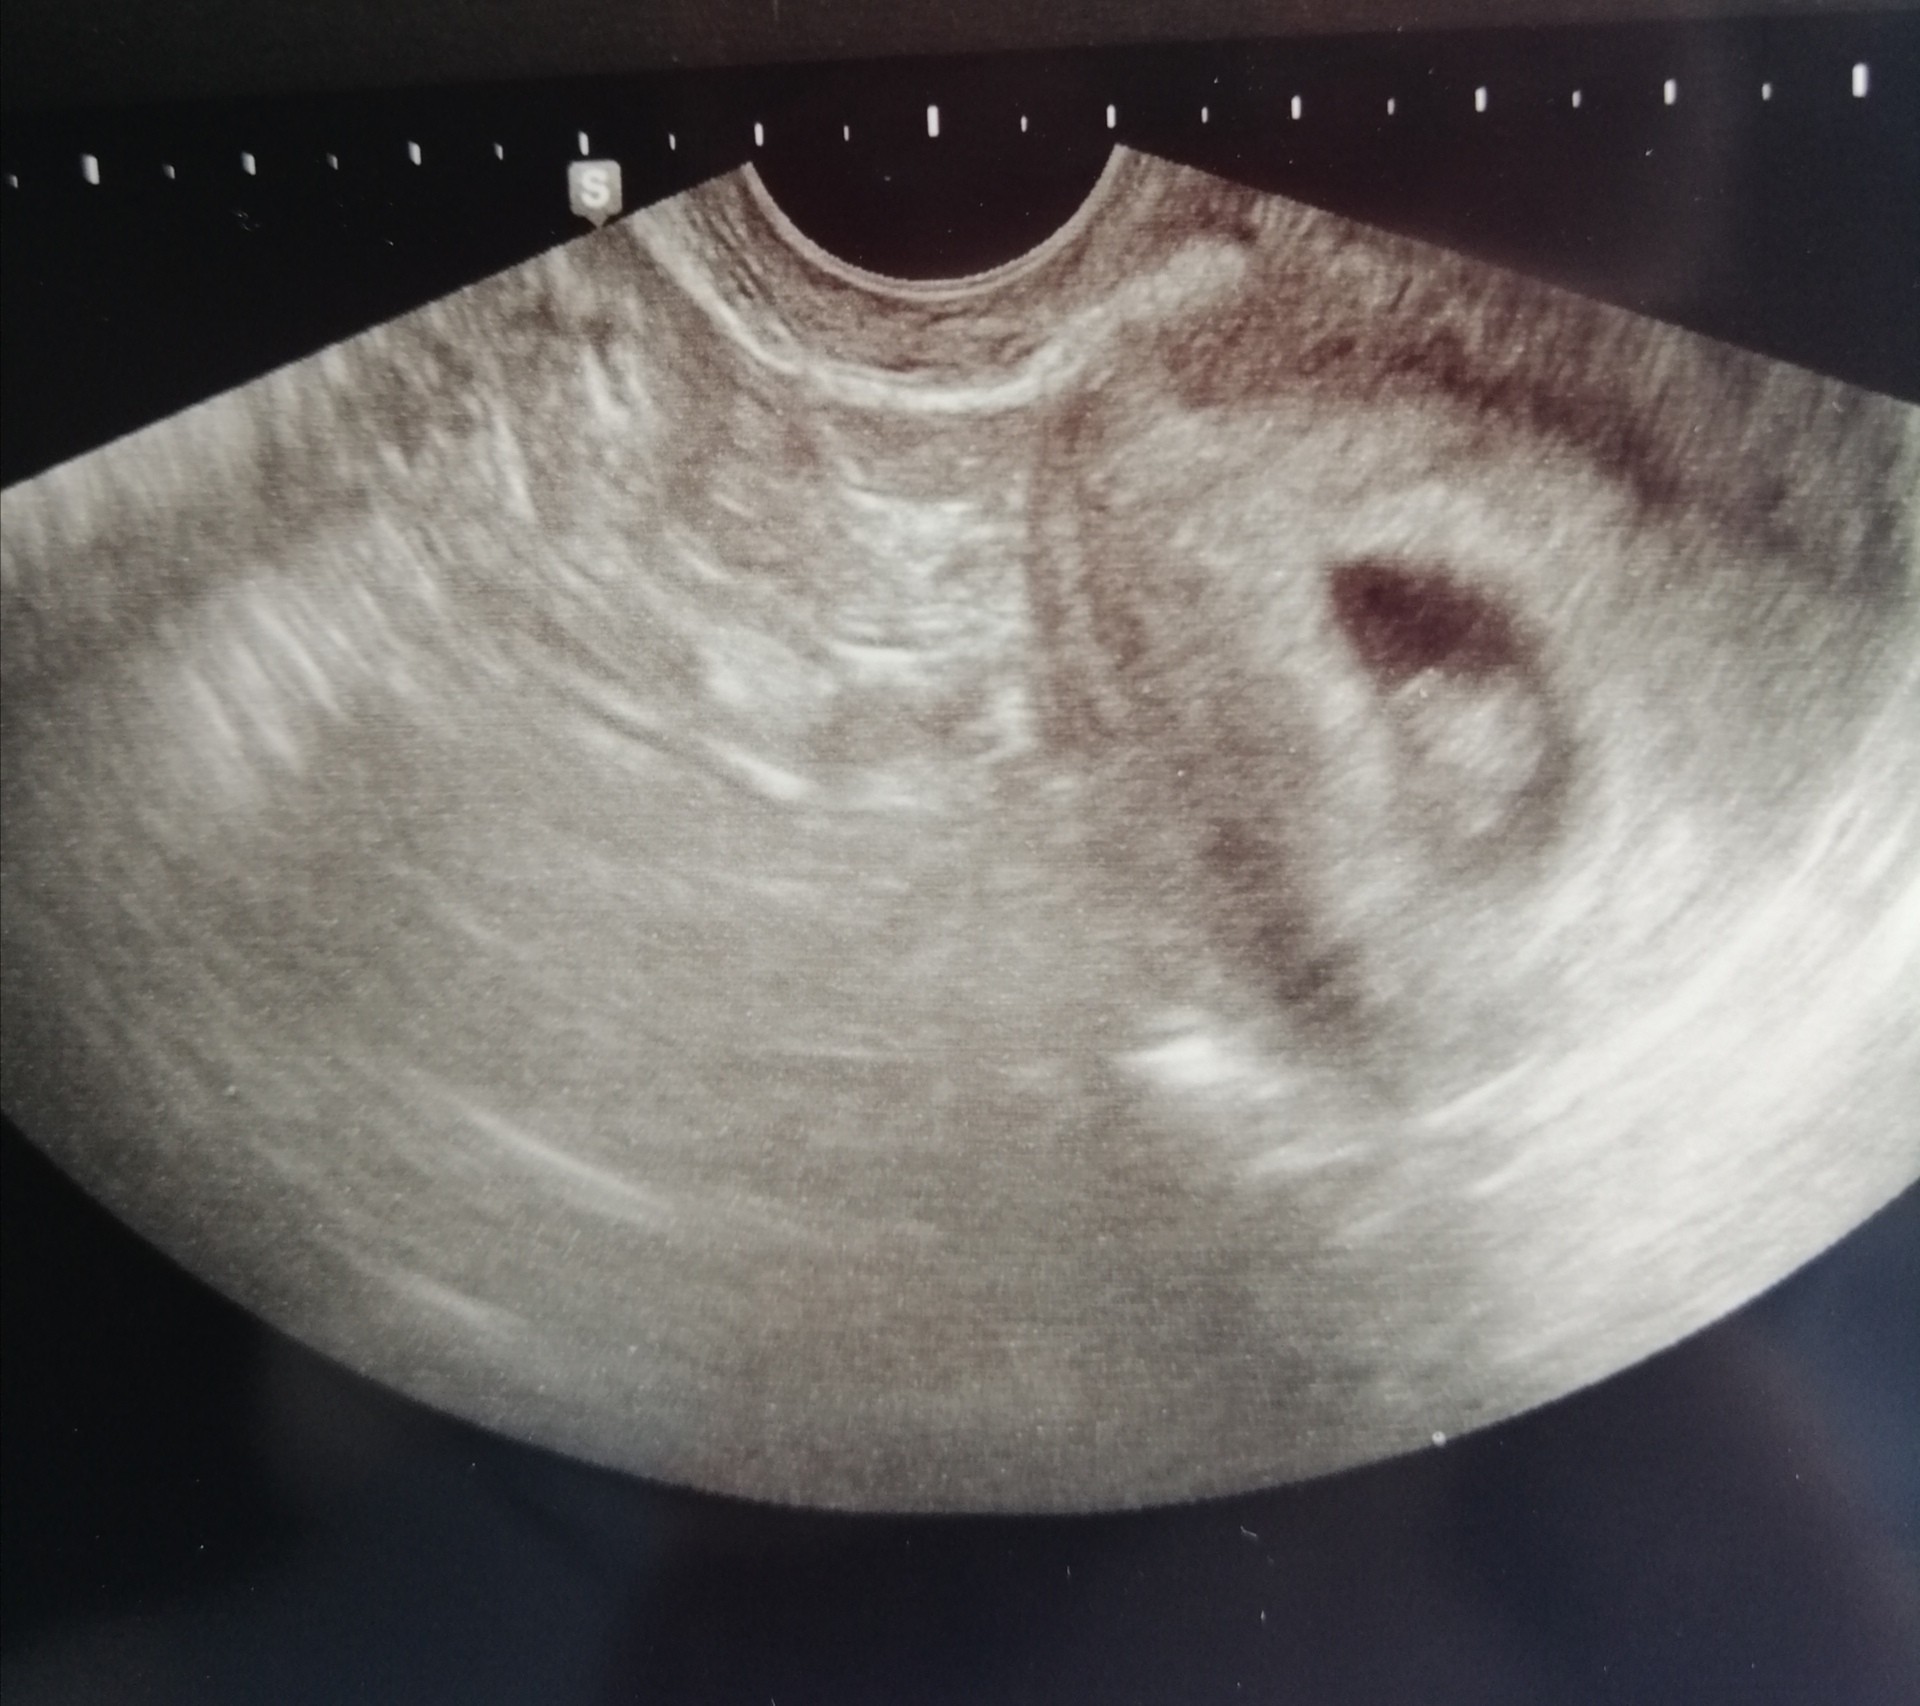

Chwale się moja fasolką [emoji3590] serduszko bije [emoji3590] 7tc [emoji3059]

Cudowny widokChwale się moja fasolką ❤ serduszko bije ❤ 7tc![]()